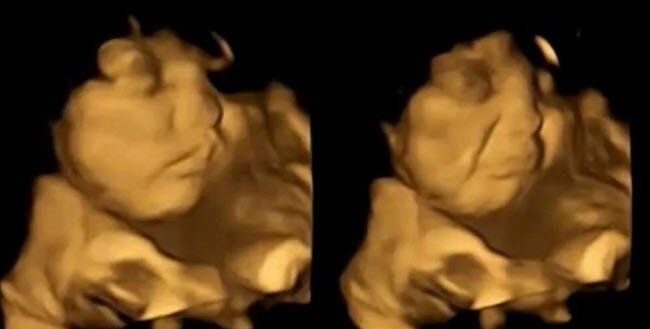

u003cbu003eANNE KARNINDAKİ BEBEKLER ANNELERİ HAVUÇ YİYİNCE GÜLÜMSÜYORu003c/bu003eYeni bir araştırma, bebeklerin daha anne karnındayken farklı tatlara tepki vermeye başladığını gösterdi. Durham Üniversitesi'nden araştırmacılar, 100 hamile kadın üzerinde yaptıkları çalışmada, dört boyutlu ultrasonla anneleri sebze yediğinde bebeklerin verdikleri tepkileri ölçtü. Sonuç dikkat çekiciydi!

Bebekler, anneleri havuç yedikten kısa süre sonra gülümserken, anneleri lahanayı tercih ettiğinde yüzlerini buruşturdu. Bulgular, hamile kadınların yediklerinin doğumdan sonra bebeklerinin tat tercihlerini etkileyebileceğini gösteriyor. Araştırmacılara göre, sonuçların sağlıklı beslenme alışkanlıkları oluşturmada etkileri olabilir.

ARAŞTIRMA EKİBİNİN BAŞINDA BİR TÜRK VARKadınlar havuç yediğinde fetüsler gülümserken, laha kapsülü fetüslerin yüzlerini buruşturmalarına yol açtı. Araştırmayı yapan ekibin başındaki isim Beyza Üstün'dü. Üstün, Henüz doğmamış bebeklerin lahana ve havuç tatlarına verdiği tepkileri görmek ve bunları ebeveynleriyle paylaşmak inanılmazdı dedi.